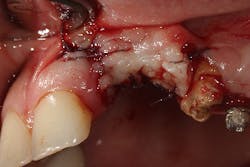

This patient presented with an unrestorable tooth No. 10 due to severe caries (figure 1). Prior to tooth extraction, the patient was informed that in order to avoid having a large defect, additional bone and soft-tissue grafting would be necessary. This type of augmentation would require additional time and finances, as well as increased surgical visits and appointments. The patient was informed that failure to undergo these procedures might result in (1) longer restorations, (2) the need for gingival ceramics, (3) inability to clean the prosthesis, and (4) increased forces on the implant because of the increased crown-to-implant ratio.

Tooth No. 10 was extracted. The socket was disinfected with chloramine-T gauze. An immediate implant (4.3 mm x 10 mm with a 5 mm healing screw) was placed (figure 2).